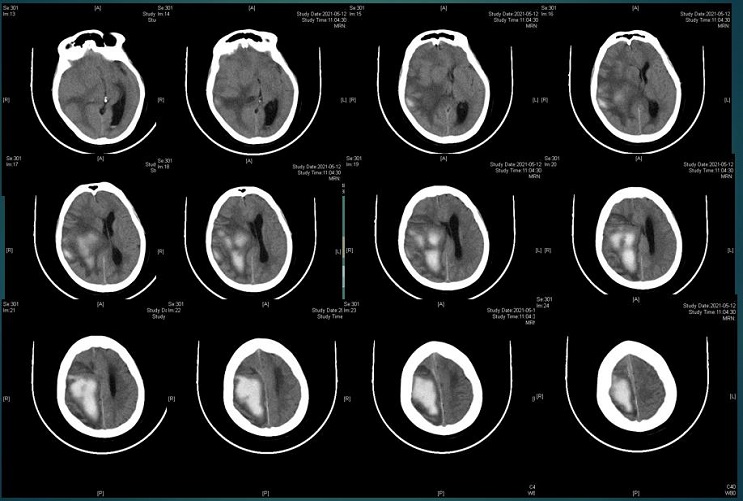

入住神经内科。2016.06.09 CT示出血量约35 ml。

2016.06.09 CT